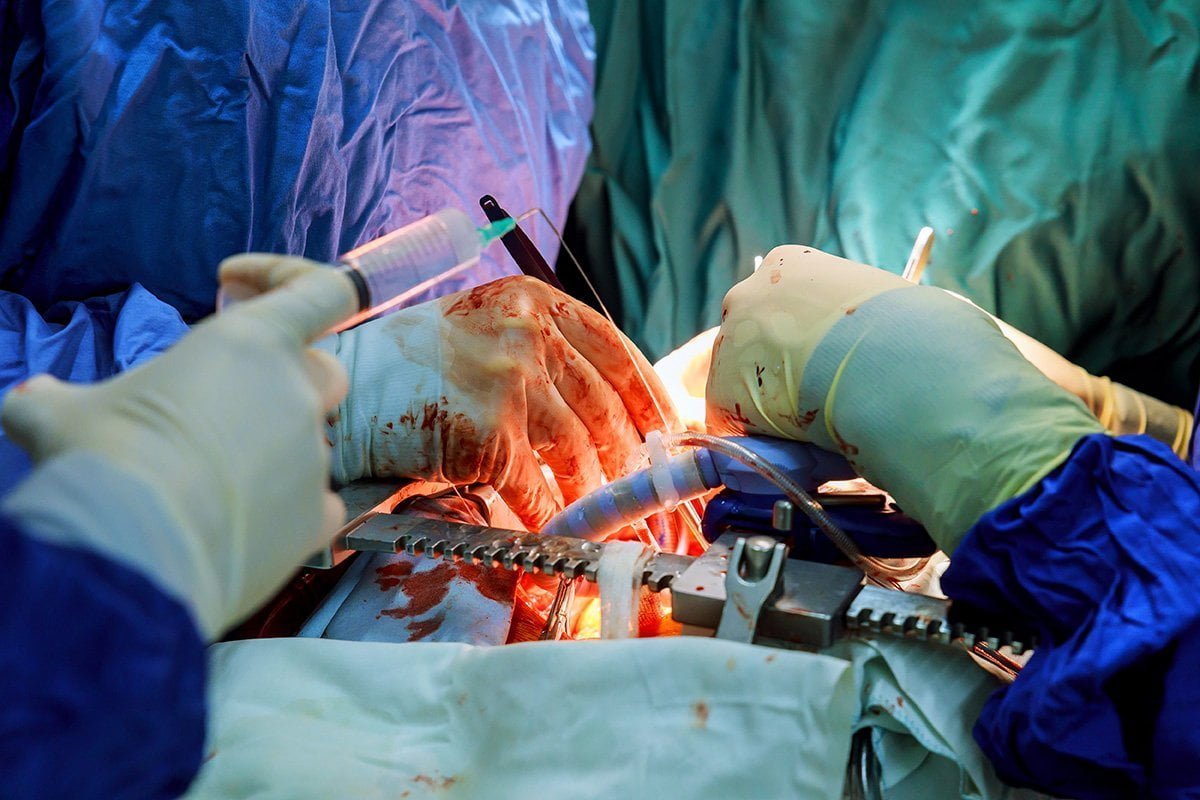

Dr. Surinder Bazaz completed his medical education (MBBS and MS) from Rajasthan University and MCH (cardiac surgery) from PGI Chandigarh. He has been associated with finest medical institutes like Escorts (14 years) and Apollo (more than 26 years) before joining Medanta – The Medicity. He specialises in the field of Vascular, Cardio (Thoracicis) and has been an integral part of Medanta’s CTVS team. Though his association with Medanta is not as lengthy as with other organizations, however, his vast experience has made him a key personnel in all kinds of routine adult cardiac & thoracic surgery.